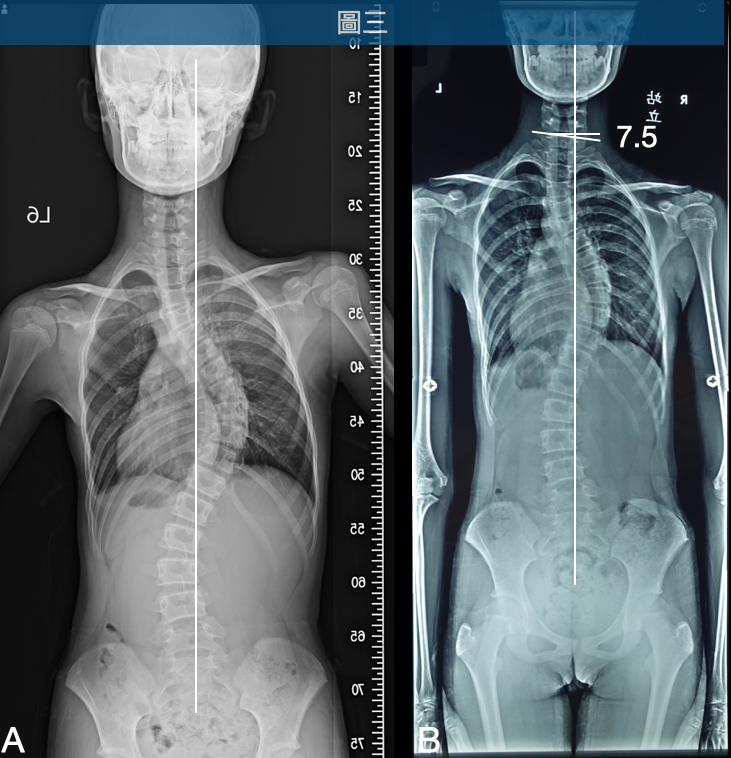

13歲女性,12歲時由家長發現姿勢異常,經由X光片確認胸椎35度、腰椎27度的中度脊椎側彎(圖一A),便開始接受一週一次的德國Schroth(許瑞氏/施羅思/施羅特)脊椎側彎運動治療,將近一年的時間,中間因疫情中斷2個月左右的治療,胸椎側彎惡化到60度、 腰椎側彎37度(圖一B)。

圖一 初次發現側彎時胸椎側彎35度、腰椎側彎27度(A),經過一週一次的德國Schroth側彎矯正運動 ,一年後胸椎側彎惡化到60度、腰椎側彎增加到37度(B)